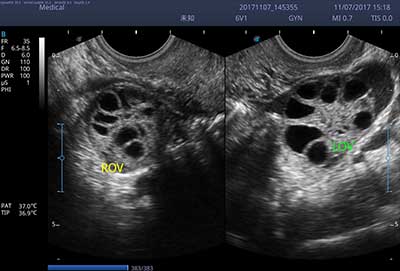

E3便携式彩色多普勒超声诊断系统拥有专业超声技术平台、高度集成化的硬件模块和结构设计、简便的操作流程、支持三探头接口全激活,兼顾了优质图像、轻便机身以及台便两用的临床使用需求。无论在常规超声科门诊检查,还是在急诊、麻醉、ICU、户外等各种应用场景。都能给您带来流程的操作体验。